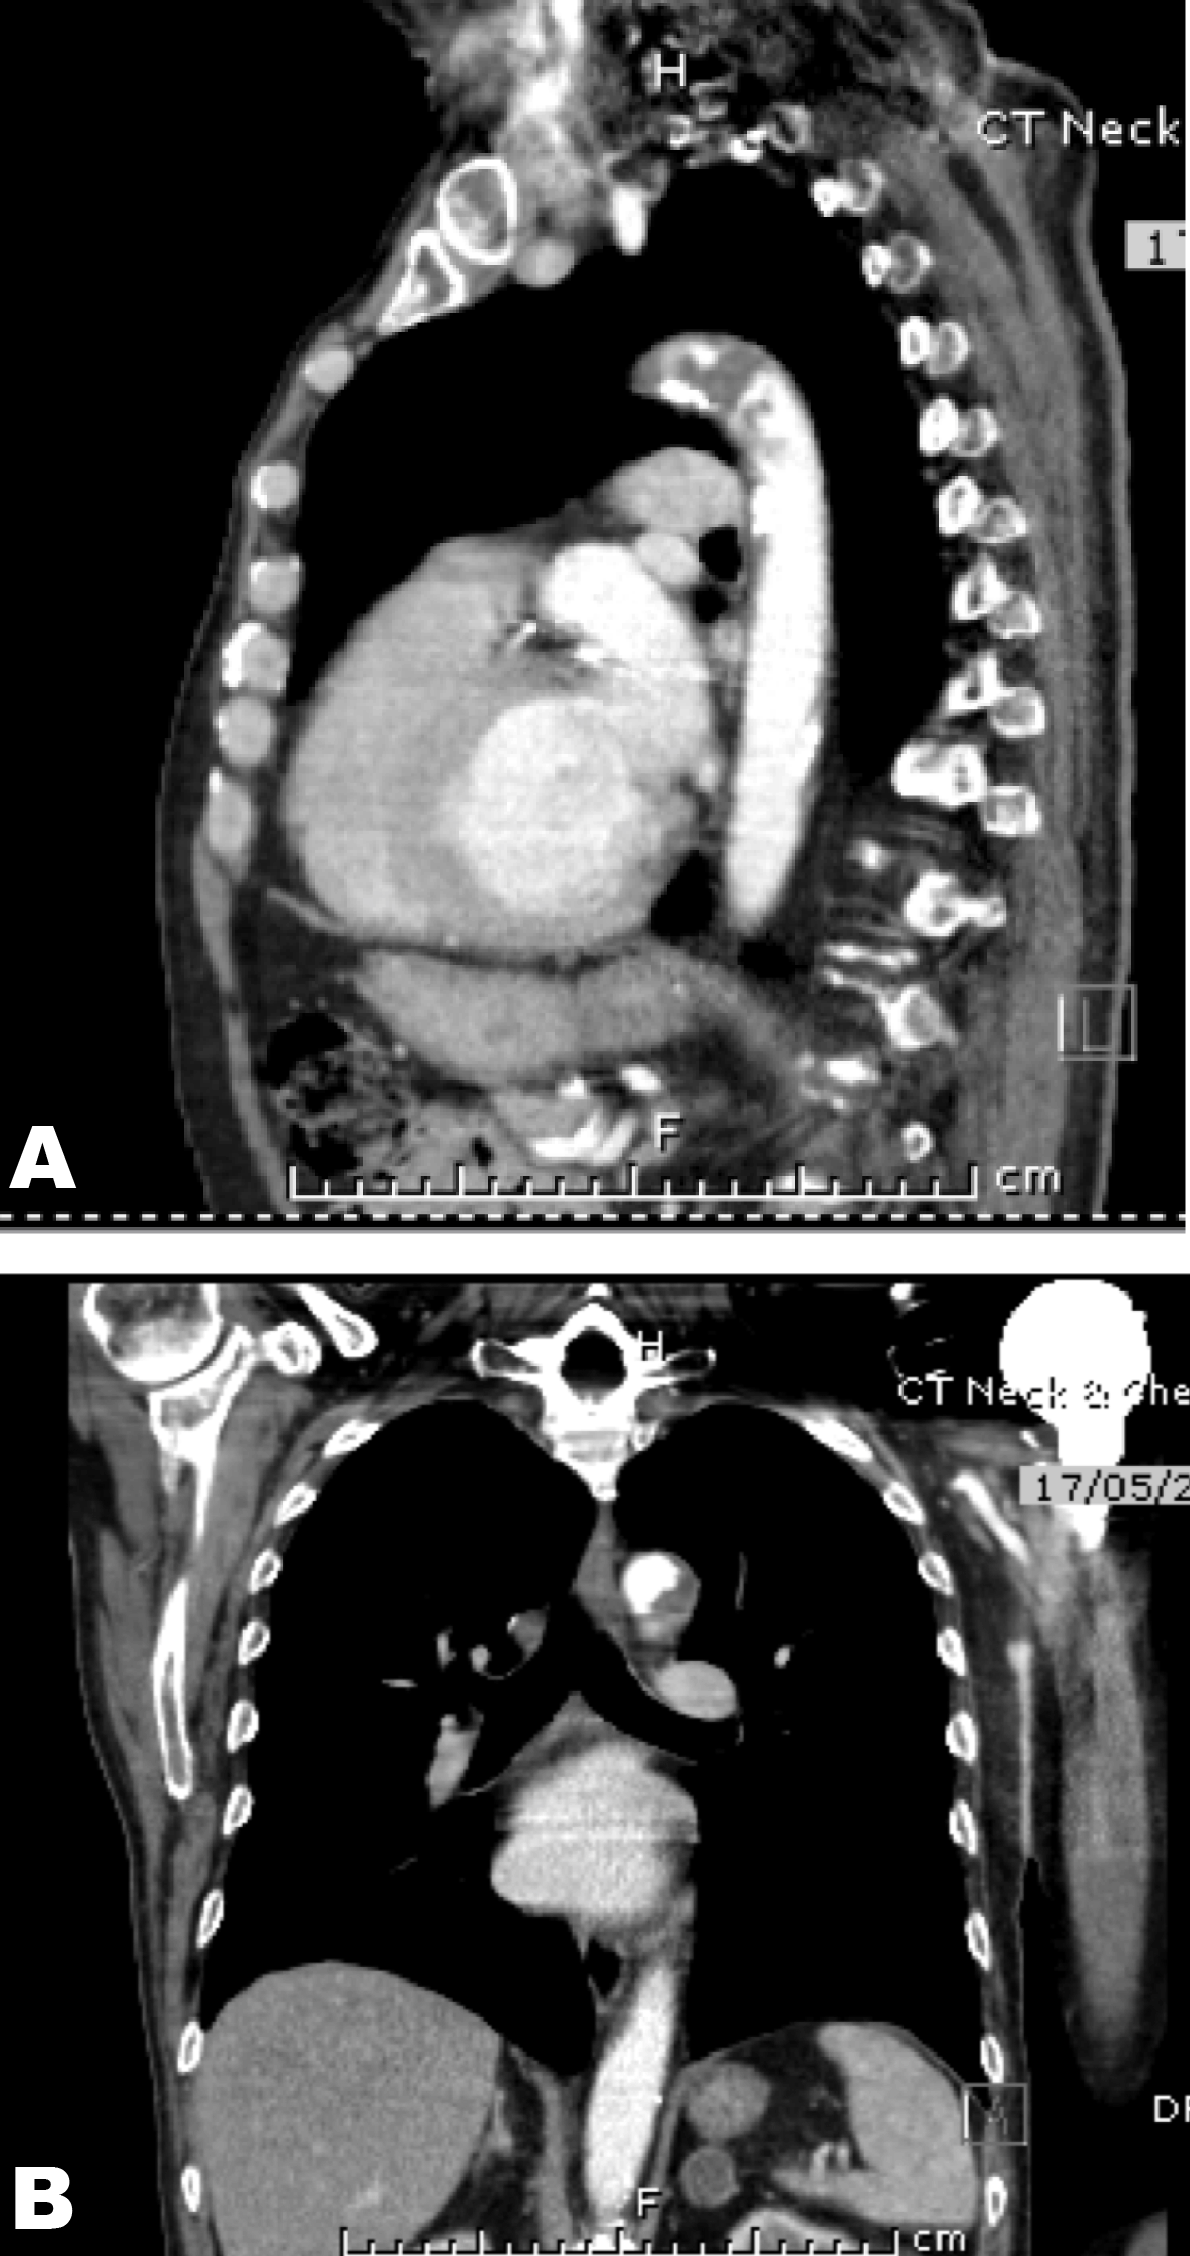

A 73-year-old male with metastatic sarcomatoid carcinoma underwent a restaging computed tomography (CT) scan that incidentally identified complete occlusion of the left common carotid at its origin and narrowing of the origin of the right brachiocephalic artery. (Figure 1) Mucosal thickening was noted with dissection through the mucosa and atheromatous plaques in the aortic arch with a pedunculated 1.9 cm thrombus. (Figure 2 A–B) The lesion was suspicious for metastasis.

Figure 1: Normal right common carotid artery. Complete occlusion of the left common carotid artery.